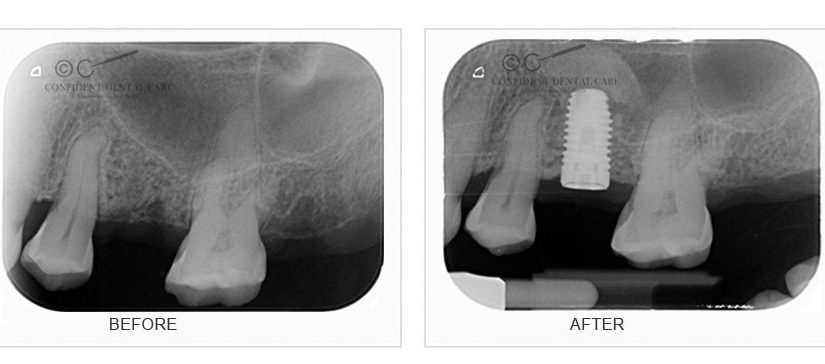

Implants X-ray